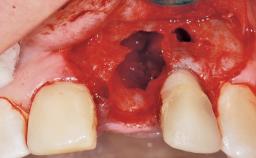

A 30-year-old female patient was referred to the office for the treatment of tooth 11. Her chief concern at the initial visit was to inquire, “Why is my tooth pink?” Upon clinical examination, it was determined that tooth 11 had a previous history of trauma and that the clinical crown had become noticeably pink in color as a result of internal resorption. This diagnosis was confirmed radiographically, indicating a large radiolucency involving the central and distal portions of the clinical crown. It was determined that restoration of this tooth was not possible, and that extraction was indicated. The presence of a mid-line diastema, which the patient wanted to reproduce, directed the treatment plan for tooth replacement utilizing a dental implant.